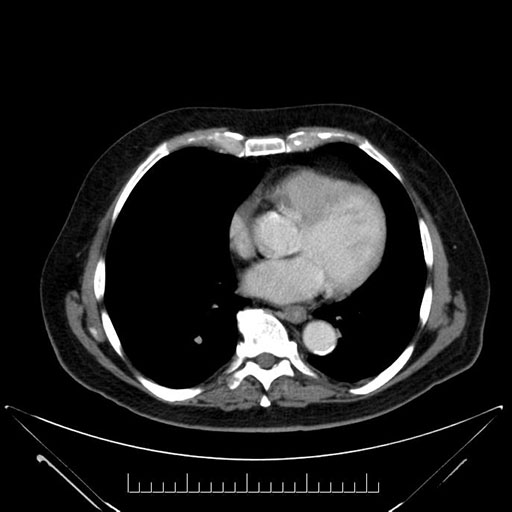

Axial - 3 months prior